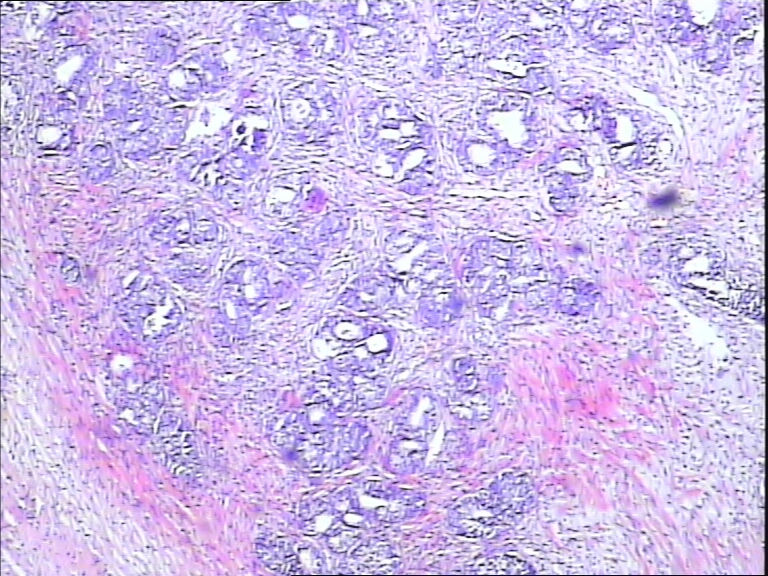

前列腺,请教,急!

图1

前列腺够癌吗?